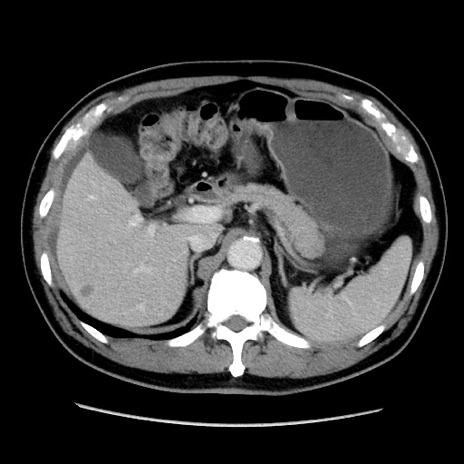

症例16(横断像)

【症例】 70歳代男性

【主訴】 腹痛、嘔吐

【現病歴】 約1ヶ月前より間欠的に腹痛と嘔吐あり、当院消化器内科を受診したところCTで多発する肝臓のLDAを指摘され、精査中であった。以降は消化器症状は安定していたが、2日前より嘔気と腹痛があり、同日より排便・排ガスが消失した。改善認めず、 本日、救急外来を受診した。

【既往歴】 大腸ポリープ切除後。

【身体所見】意識清明・会話良好、BT 36.3℃、BP 127/80mmHg、 P 80bpm、腹部:膨満あり、平坦・軟、上腹部正中および下腹部正中に圧痛あり、反跳痛なし、筋性防御なし。

【データ】WBC 7200、CRP 0.77